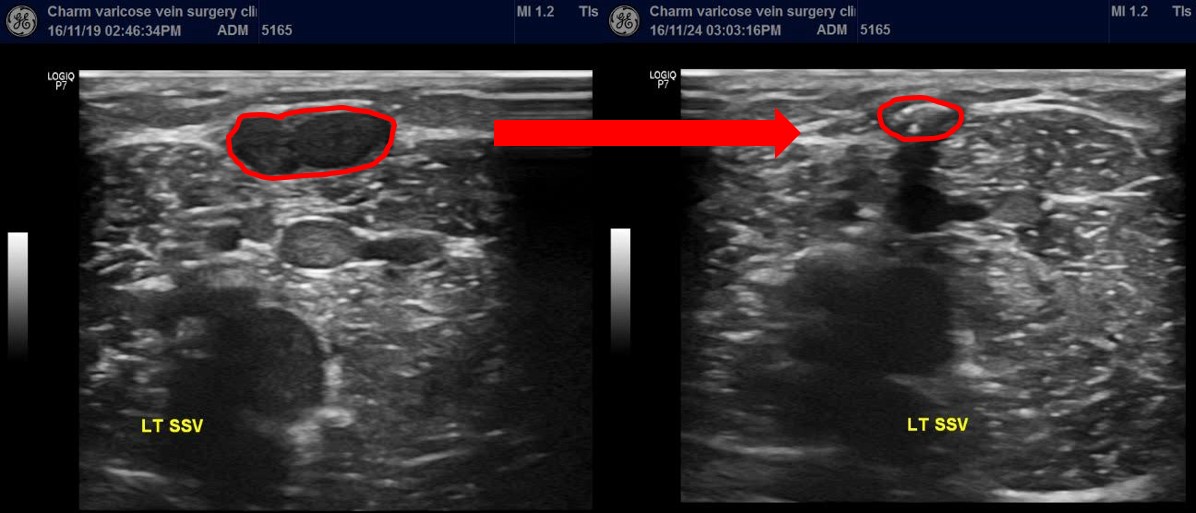

수술 직후의 변화입니다

1.4cm 직경가량의 혈관이 시술 직후 6시간뒤

서서 초음파를 확인하였을때 즉각적으로 유착된 것이 보입니다